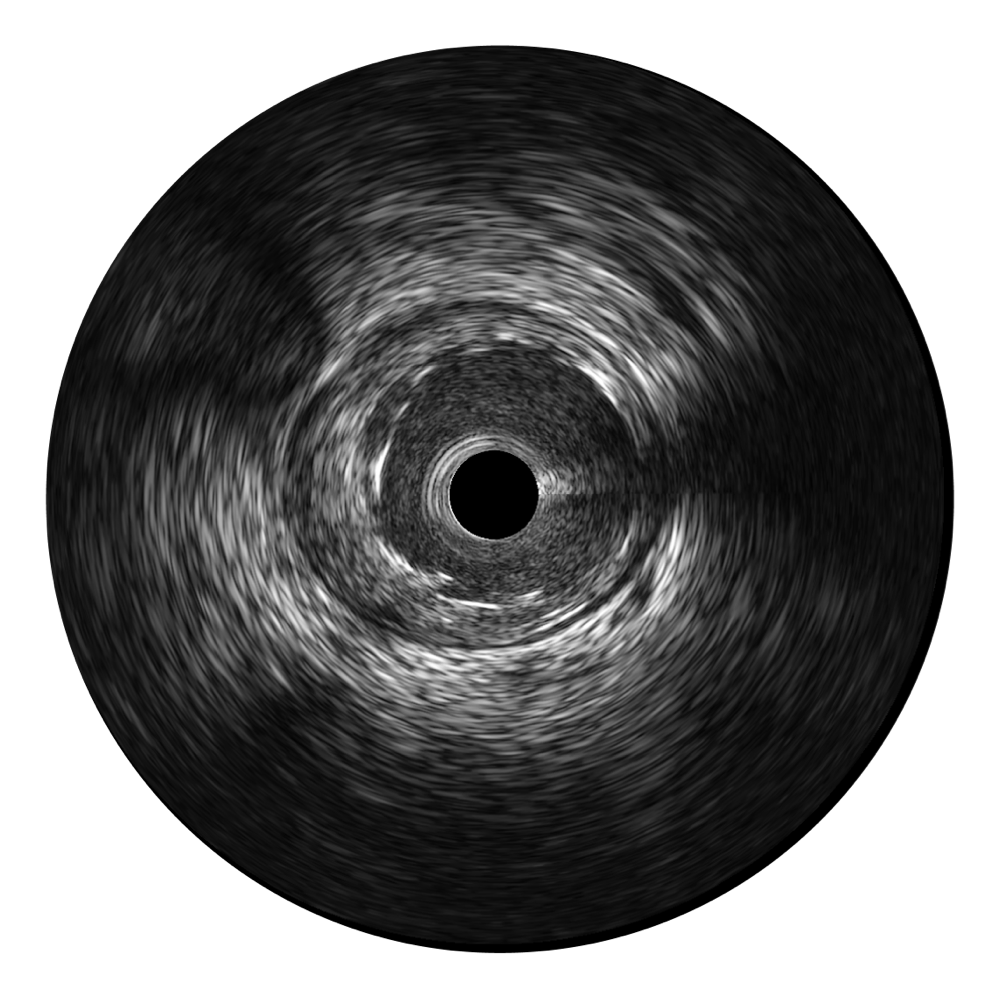

• 传统IVUS图像

对比传统IVUS导管成像,亚星官网宽频IVUS图像的近场支架梁显影更细腻,远场中膜外血管仍清晰可辨,兼顾远中近,兼顾分辨力与穿透深度